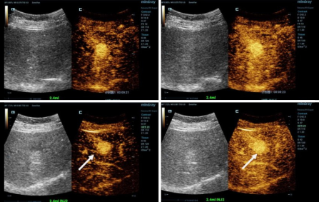

Le 30 octobre à Bali, en Indonésie, Mindray a organisé le Forum de l'échographie 2022 pour l'Asie du Sud et du Sud-Est, sur le thème "Construire des ponts, relier des visions". Plus de 150 participants d'Indonésie, des Philippines et de Thaïlande ont participé à ce forum universitaire, où des spécialistes ont partagé leur expertise clinique et échangé des idées sur les technologies de pointe.

Ultrasound